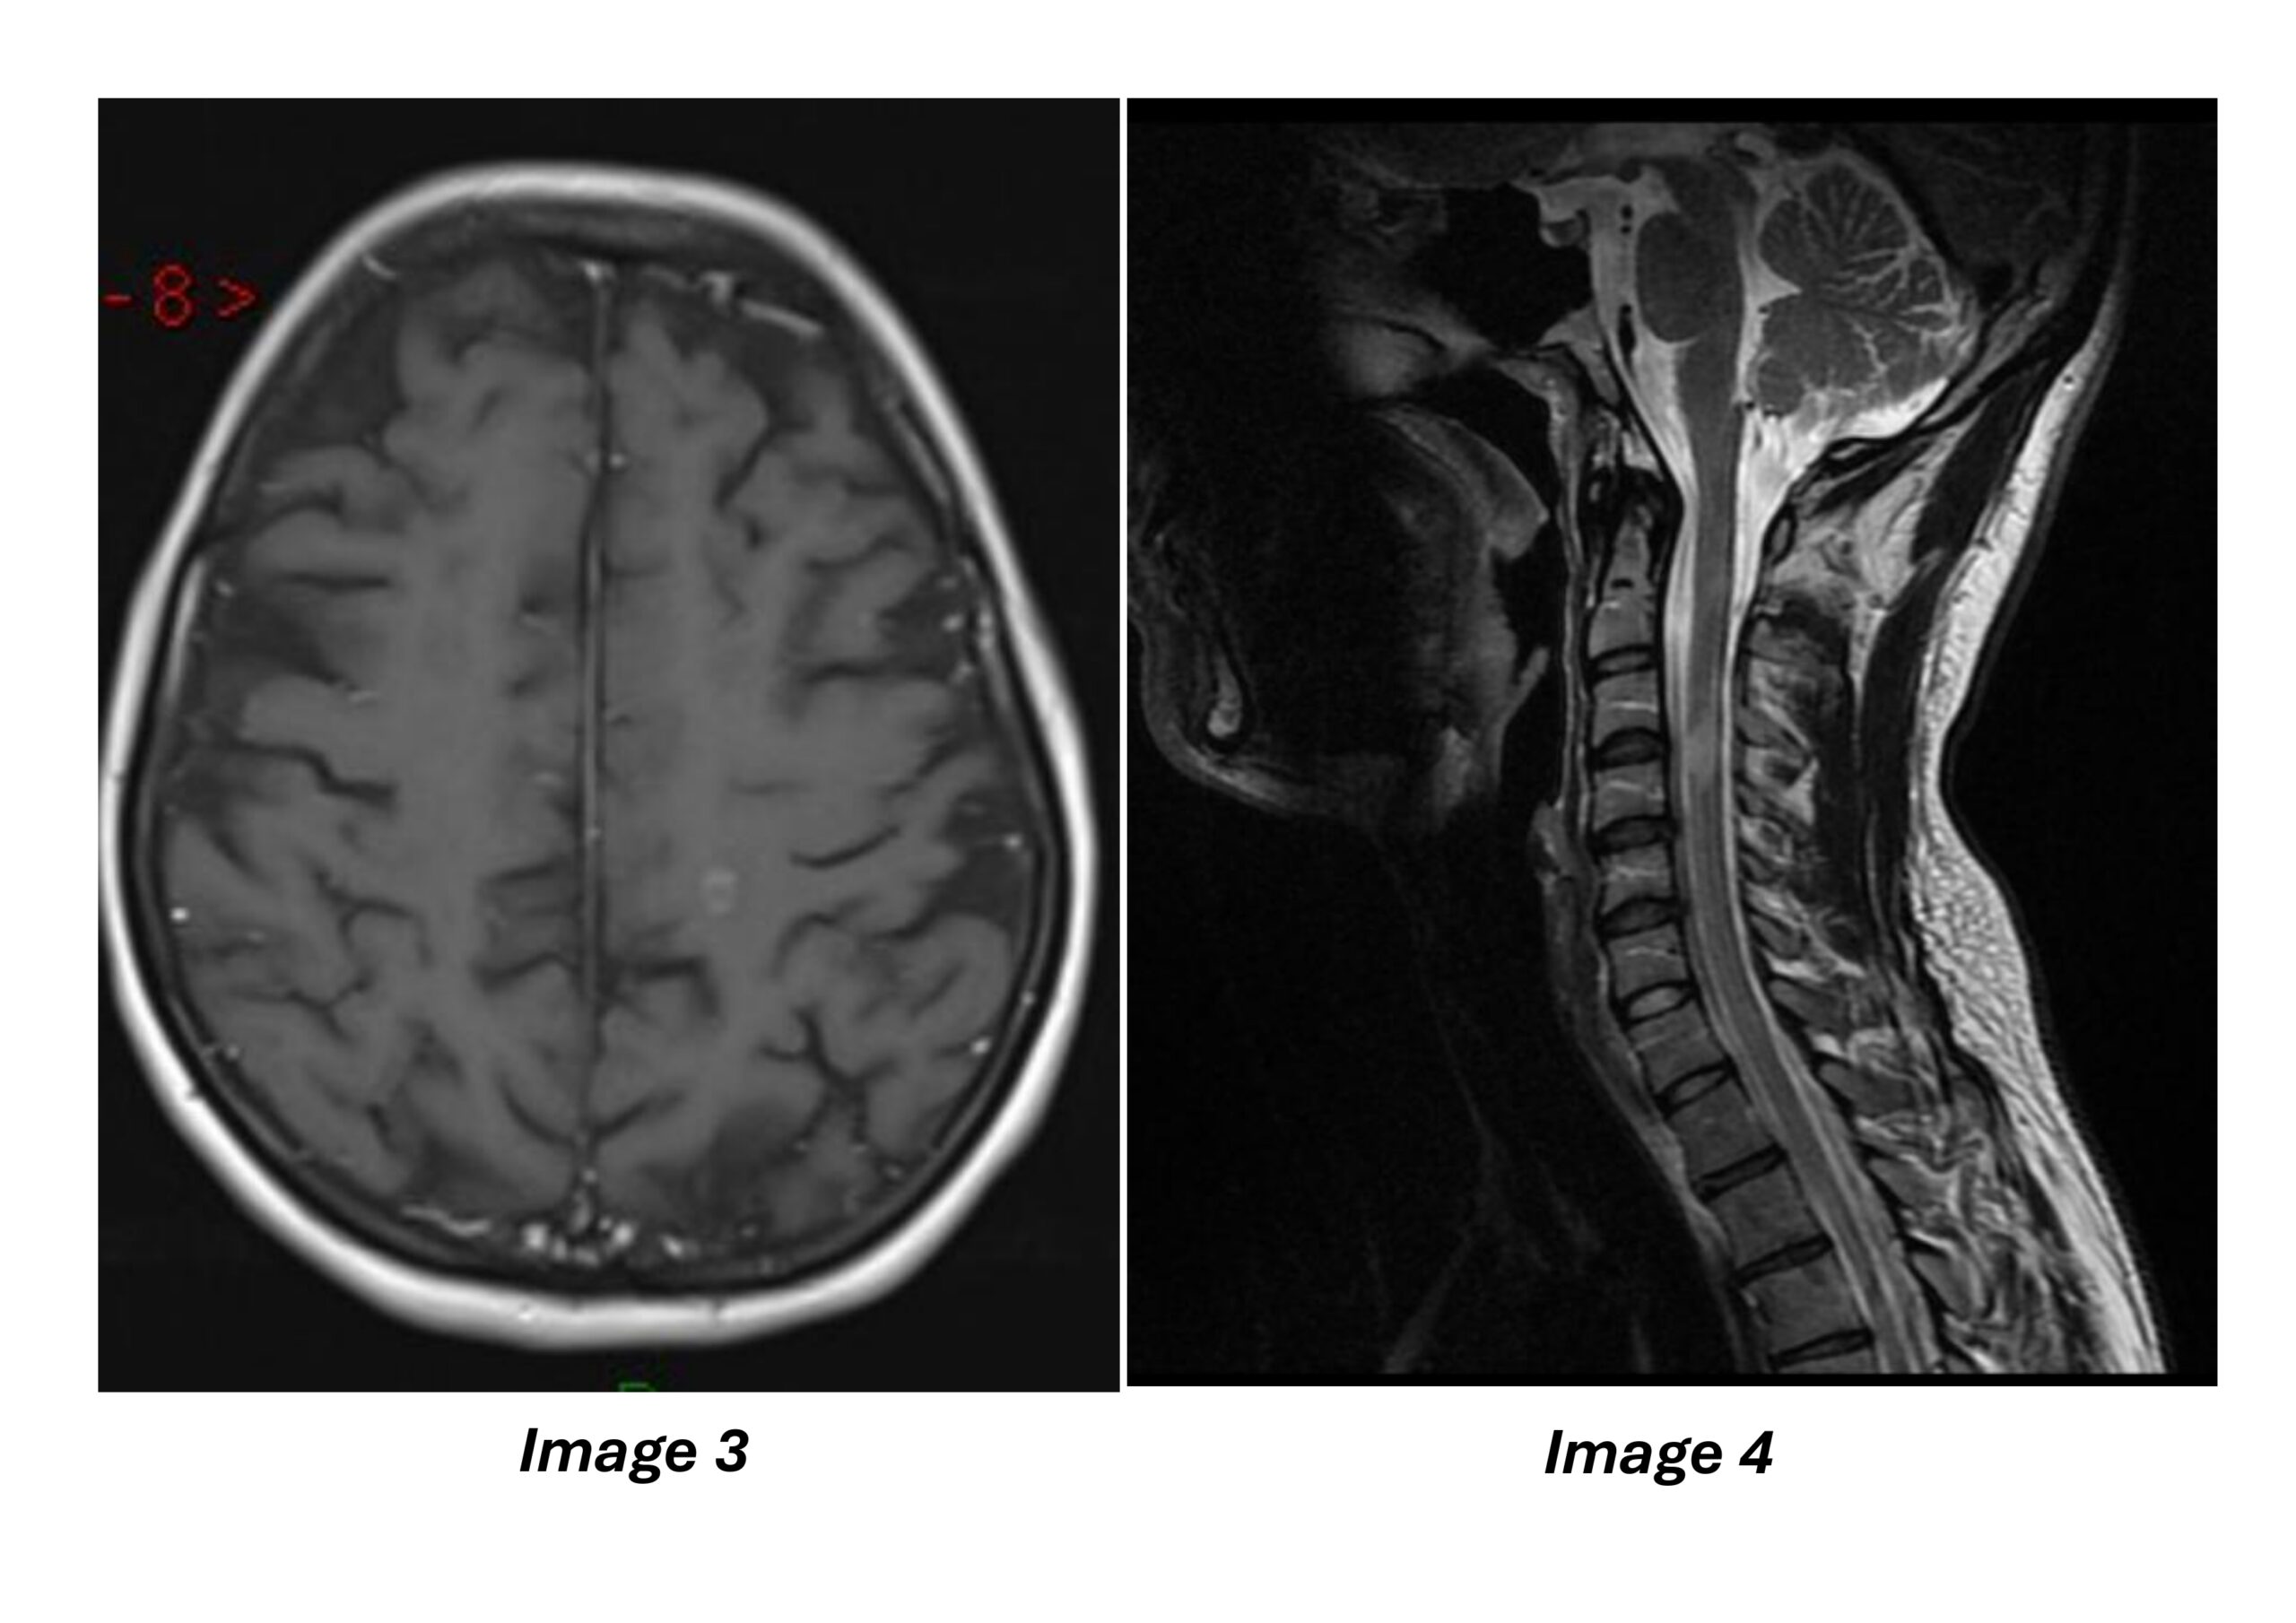

Décrire les 4 coupes d’imagerie.

Proposer un diagnostic, en précisant si vous pouvez ou non le poser à partir de cette imagerie et sur quels arguments.

Il va devoir décrire des coupes d’IRM et à partir d’elles poser le diagnostic de SEP grâce aux critères de dissémination spatiale et temporelle.

Soyez bien rigoureux : pour chaque imagerie, qu’il mentionne bien le type d’imagerie, la coupe, la séquence et l’injection si besoin. Seulement accepter hyper-signal ou hyper-intensité.